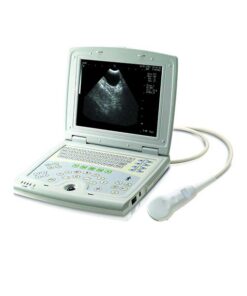

XF300 (LED) B ultrasound diagnose medical instrument

Portable LED screen ultrasound

XF300 (LED) B ultrasound diagnose medical instrument

The fully digital ultrasound image diagnostic equipment,

12in LCD screen main unit with one probe |

Real photos